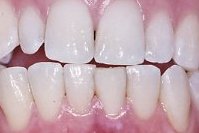

Die Abb. 1 bis 4 sollen als anschauliche Beispiele für gesunde und kranke Fundamente dienen.

Ein 31 Jahre alter Patient zeigt einen starke Zahnfleisch-Rückgang im Oberkiefer (Abb. 1 und 3) und wir beschliessen, diese Rezessionen zu behandeln.

Der Erfolg der Behandlung ist deutlich in den Abb. 2 und 4 zu sehen. Sehr augenfällig konnte die Situation um den Eckzahn im linken Oberkiefer verbessert werden (vergleiche dazu Abb. 3 vorher und Abb. 4 nachher).